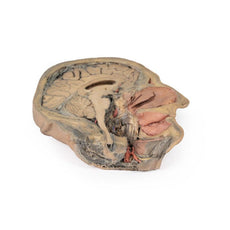

Cranial Cavity: The left and right orbits have been opened to reveal the orbital nerves and vessels along with the eyes and optic nerves. The optic chiasm, optic tracts and the lateral geniculate bodies are retained thus showing a large part of the visual pathways. The brainstem is cut at the level of the superior colliculi on the left and slightly lower on the right. The olfactory tracts and bulbs are also demonstrated. The origins of many of the cranial nerves from the brainstem are clearly visible.

Cranial Cavity: The left and right orbits have been opened to reveal the orbital nerves and vessels along with the eyes and optic nerves. The optic chiasm, optic tracts and the lateral geniculate bodies are retained thus showing a large part of the visual pathways. The brainstem is cut at the level of the superior colliculi on the left and slightly lower on the right. The olfactory tracts and bulbs are also demonstrated. The origins of many of the cranial nerves from the brainstem are clearly visible.